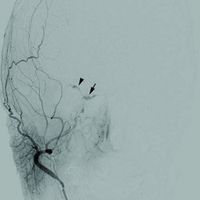

ويستند ذلك إلى التصوير بالرنين المغناطيسي، تصوير الأوعية بالرنين المغناطيسي والمسح الضوئي. تصوير الأوعية بالطرح الرقمي الدماغي (DSA) يعزز رؤية الناسور.